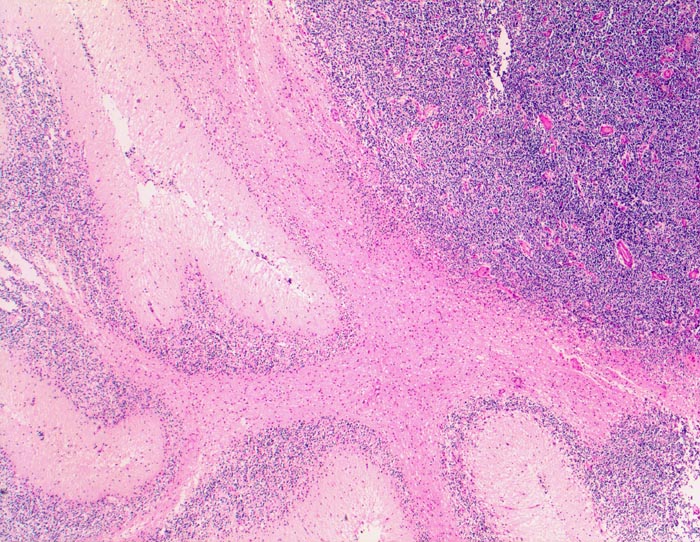

Wegen der hohen Zelldichte und der hohen Kern-Zytoplasmarelation erscheinen die Tumoren in der HE Färbung blau. Medulloblastome müssen differentialdiagnostisch von morphologisch ähnlichen kleinzelligen undifferenzierten Karzinomen und Lymphomen abgegrenzt werden. Das klassische Medulloblastom besteht aus dicht gepackten Zellen mit runden bis ovalen oder karottenförmigen stark hyperchromatischen Kernen umgeben von wenig Zytoplasma. Runde Zellen mit weniger dichtem Chromatin sind oft beigemischt. Zahlreiche Mitosen, flächenhafte Nekrosen und Apoptosen sind typisch. In weniger als einem Drittel der Fälle findet man die typischen Homer-Wright Rosetten. Diese bestehen aus ringförmig angeordneten Tumorzellkernen um ein fibrilläres Zentrum aus Zytoplasmafortsätzen.

• Scharf begrenzter rundlicher sehr zellreicher (deshalb blauer) Tumor.

• Monomorpher Zellrasen mit hyperchromatischen ovalen oder karottenförmigen Zellkernen.

• Kaum erkennbares Zytoplasma.

• Homer-Wright Rosetten aus ringförmig angeordneten Tumorzellkernen um ein fibrilläres Zentrum aus Zytoplasmafortsätzen.